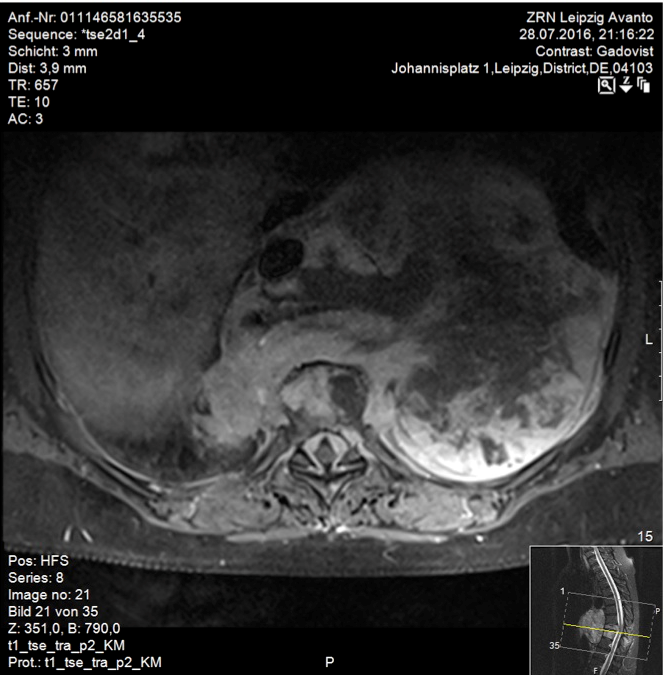

A 59-year-old woman presented with persistent pain in the thoracic spine after low energy trauma 6 weeks ago. X-ray imaging showed vertebra compression fracture of Th9 with kyphosis of 20°. The patient had a history of three strokes, 15 and 13 years ago, with residual paralysis on the right side. She did not report of new neurological disability after trauma: no new motor dysfunction, no long tract signs, neither bladder nor bowel dysfunction. There was no history of malignancy in her family. MRI studies revealed a solid mass of 16x14x12 cm in the inferior posterior mediastinum on the left side with infiltration of Th9 and Th10 vertebral body and spinal canal infiltration with myelon compression (Figure 1 [Fig. 1], Figure 2 [Fig. 2]). Staging procedure including total spine MRI, abdominal and chest computed tomography (CT), cranial CT, and PET CT did not show distant metastasis. The interdisciplinary tumor board decided to perform a transthoracic needle aspiration biopsy first. The histopathological examination could not define a clear diagnosis. Therefore an open biopsy was performed. This result was not clear, too. At last, pleomorphic rhabdomyosarcoma or liposarcoma with rhabdomyogenic dedifferentiation were discussed. The proliferation index Ki67 was 70%, meaning high-grade sarcoma. Trimodality treatment was proposed: surgery with “en-bloc” resection followed by adjuvant multidrug chemotherapy and radiation beam therapy. The day after biopsy, the patient suddenly developed an ascending sensory spinal cord injury. We decided for a two-stage surgery, starting with immediate posterior decompression and stabilization: We performed a posterior decompression with complete resection of the posterior parts of the Th9 and Th10 vertebra with spinal canal clearance. Long segment stabilization was performed three levels above and three levels below (Figure 3 [Fig. 3]). After a few days of recovery the anterior procedure followed (Figure 4 [Fig. 4]). Via thoracolumbophrenotomy an “en bloc” resection including TH9 and Th10 vertebral body as well as 2 level cage reconstruction of the anterior column was performed (Figure 5 [Fig. 5], Figure 6 [Fig. 6]). The patient recovered quite well after surgery: no problems of wound healing, no new neurological deficits, sensory deficit improved. Adjuvant chemotherapy started 4 weeks after surgery with the first of 3 cycles in a 21 days period. Unfortunately chemotherapy had to be reduced and later stopped due to major side effects. A radiation beam therapy with total radiation dose of 60 Gy followed. The patient did well at 3 month and 6 month follow-up, showing no new neurological deficits, less pain. MR imaging after 6 month did not show local recurrence and PET CT did show no proof of relapse.

Figure 2: T1-weighted, contrast enhanced transverse MR image of the thoracic spine. Inhomogeneous gadolinium distribution. Solid mass in the posterior inferior mediastinum with spinal canal infiltration and myelon compression.